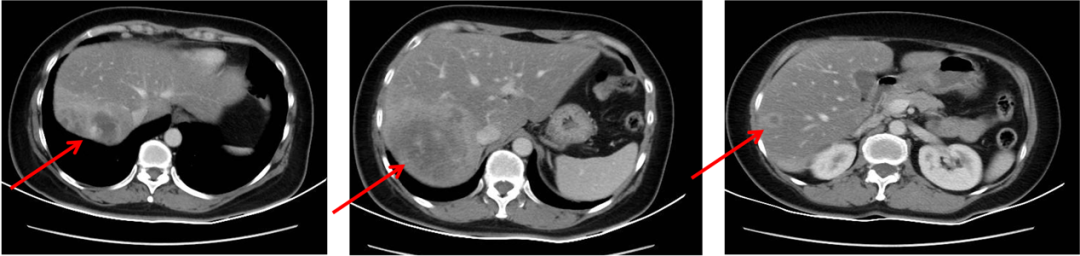

2013年6月30日腹部CT:肝右后叶病灶并肝内多发子灶,考虑M,病灶总范围8.0*5.8cm,其病灶周围可见多发异常廓清子灶(4-5个),最大约1.6cm;

图1. 腹部CT